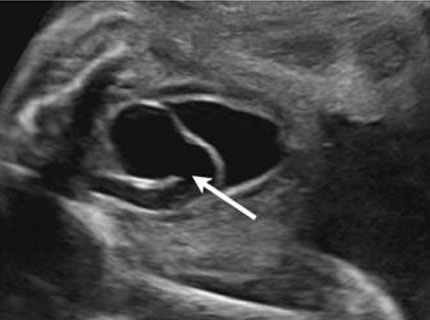

The best diagnostic clue is a dilated upper collecting system and a ureterocele within the urinary bladder (Figure 7). Kidneys should be evaluated in transverse and longitudinal planes (Figure 8).

Figure 7: Ultrasound image showing a ureterocele (part of the ureter that inserts into the bladder forming a cystic structure) in the urinary bladder [19]. Radiological images were obtained from open-access article distributed under the terms of the Creative Commons Attribution License (CC BY) [19].